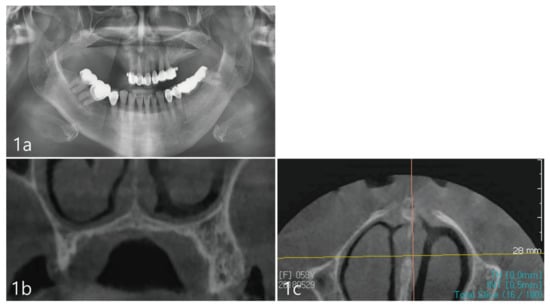

A 65-year-old female patient presented to a private dental office in Seoul, Republic of Korea, with a chief concern, to rehabilitate her posterior occlusion with the aid of dental implants. The patient self-reported as a non-smoker, with no systemic health conditions and no medications. Her medical and dental history were obtained, and the patient presented without any nasal or sinus-related symptoms. A physical head and neck examination was performed. Clinical examination revealed no intra- or extra-oral swelling or asymmetry. Past dental history revealed the loss of posterior upper right dentition due to periodontitis with concomitant vertical and horizontal bone resorption (Figure 1a) depicted in the panoramic radiograph. In comparison to the left dentate maxillary quadrant, the right maxillary bone height is significantly decreased due to vertical bone loss. The radiographic trace of the floor of the right maxillary sinus appears well-defined. However, subsequent cone beam computed tomography (CBCT) (PaX-i3D Smart, Vatech, Seoul, Republic of Korea) imaging depicts a closely positioned nasal cavity located directly apical to the ridge (Figure 1b). The coronal view clearly shows the most coronal portion of the maxillary sinus at the upper-left corner of Figure 1b, while the bucco–palatal dimension of the remaining ridge showed deficient lateral volume. The inferior meatus of the nasal cavity extended to the posterior maxilla and the lateral breadth appeared wide (Figure 1c).

Figure 1. (a). Pre-operative panoramic radiograph shows severely atrophic posterior maxilla. The maxillary sinus is not well-observed. (b). Coronal view of the CBCT showing a portion of the maxillary sinus at the most upper-left corner. The ridge dimensions show deficient vertical and horizontal bone volume. (c). Axial view of the CBCT shows the inferior meatus of the nasal cavity.